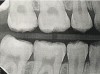

Fig 6. Three thin soft dental picks were used simultaneously for SDF proximal surface saturations in a teenaged patient (Fig 3). After 60 seconds, the treated regions were covered with 5% fluoride varnish (Fig 4). A comparison can be seen of pre-SDF-treatment bitewing films (Fig 5) and 8-month post-SDF bitewing films (Fig 6) for the patient shown in Fig 3 and Fig 4. Radiolucencies were similar or improved, except for contact of maxillary first and second molars.

Fig 3. Three thin soft dental picks were used simultaneously for SDF proximal surface saturations in a teenaged patient (Fig 3). After 60 seconds, the treated regions were covered with 5% fluoride varnish (Fig 4). A comparison can be seen of pre-SDF-treatment bitewing films (Fig 5) and 8-month post-SDF bitewing films (Fig 6) for the patient shown in Fig 3 and Fig 4. Radiolucencies were similar or improved, except for contact of maxillary first and second molars.

Interproximal insertion of SDF is demonstrated in different patients in Figure 3 through Figure 11. Various diameters and brands of soft dental picks may be used depending on the closeness of the proximal surfaces and ease of insertion; for example, some picks are designed for use in wider spaces between teeth. This protocol also offers versatility. Figure 3, for example, shows the simultaneous use of three thin soft dental picks to saturate proximal surfaces with SDF in a teenaged patient; the treated regions were subsequently covered with fluoride varnish (Figure 4). This patient was initially treated in April 2019 (Figure 5), with an identical re-application 3 months later. As shown in Figure 6, the December 2019 bitewing film revealed good results with the possible exception of the contact regions of the maxillary first and second molars. New SDF application was completed in the December appointment.

The senior author's (TPC) private practice experience with soft-tip insertion of SDF into contacting proximal surfaces of teeth is that most beginning proximal surface caries lesions cease to progress, as evidenced by subsequent bitewing radiographic comparisons (Figure 3 through Figure 6, Figure 12 through Figure 18). The chances for success vary, however, depending on frequency of application, subsequent flossing by patients or adults flossing younger children, diet control, individual mouth chemistries, and use of fluorides for the topical effect. It must also be emphasized that office staff should make extensive efforts to inform children and parents that subsequent daily flossing is needed to accompany SDF treatments; otherwise, SDF applications will only delay the inevitable progression of caries. Flossing methods should be demonstrated for patients and for parents so they may see how to floss younger children. Showing them enlarged graphic photographs of flossing results may be helpful in this regard. Parents and patients should be made aware that if interproximal dental plaque accumulations persist without daily interruption by flossing, the acid insult will eventually take its toll on the proximal surfaces and caries lesions will progress to the point where restorative intervention may be required.